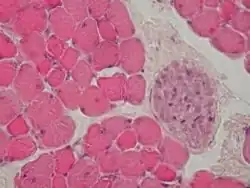

Adipose Tissue

Fat cells are found distributed throughout the body. There is very little ground substance

Skeletal Muscle